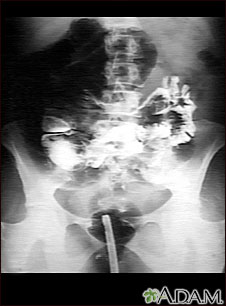

A GI series in a patient with a twisted bowel (volvulus).